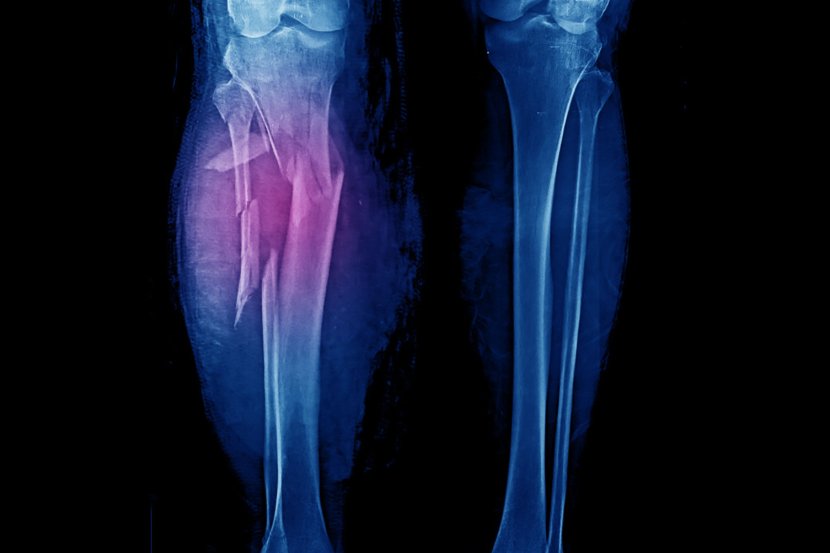

Prelomi tibije

Prelom kosti je medicinski izraz za lomljenje kosti. S obzirom na to da su tibije toliko jake, obično ih slome samo ozbiljne povrede poput saobraćajnih nesreća, padova ili drugih trauma. Simptomi preloma uključuju:

• Bol

• Otok

• Osetljivost

• Nemogućnost pomeranja noge kao obično

• Modrice ili promena boje kože

• Deformitet ili kvrga na telu.